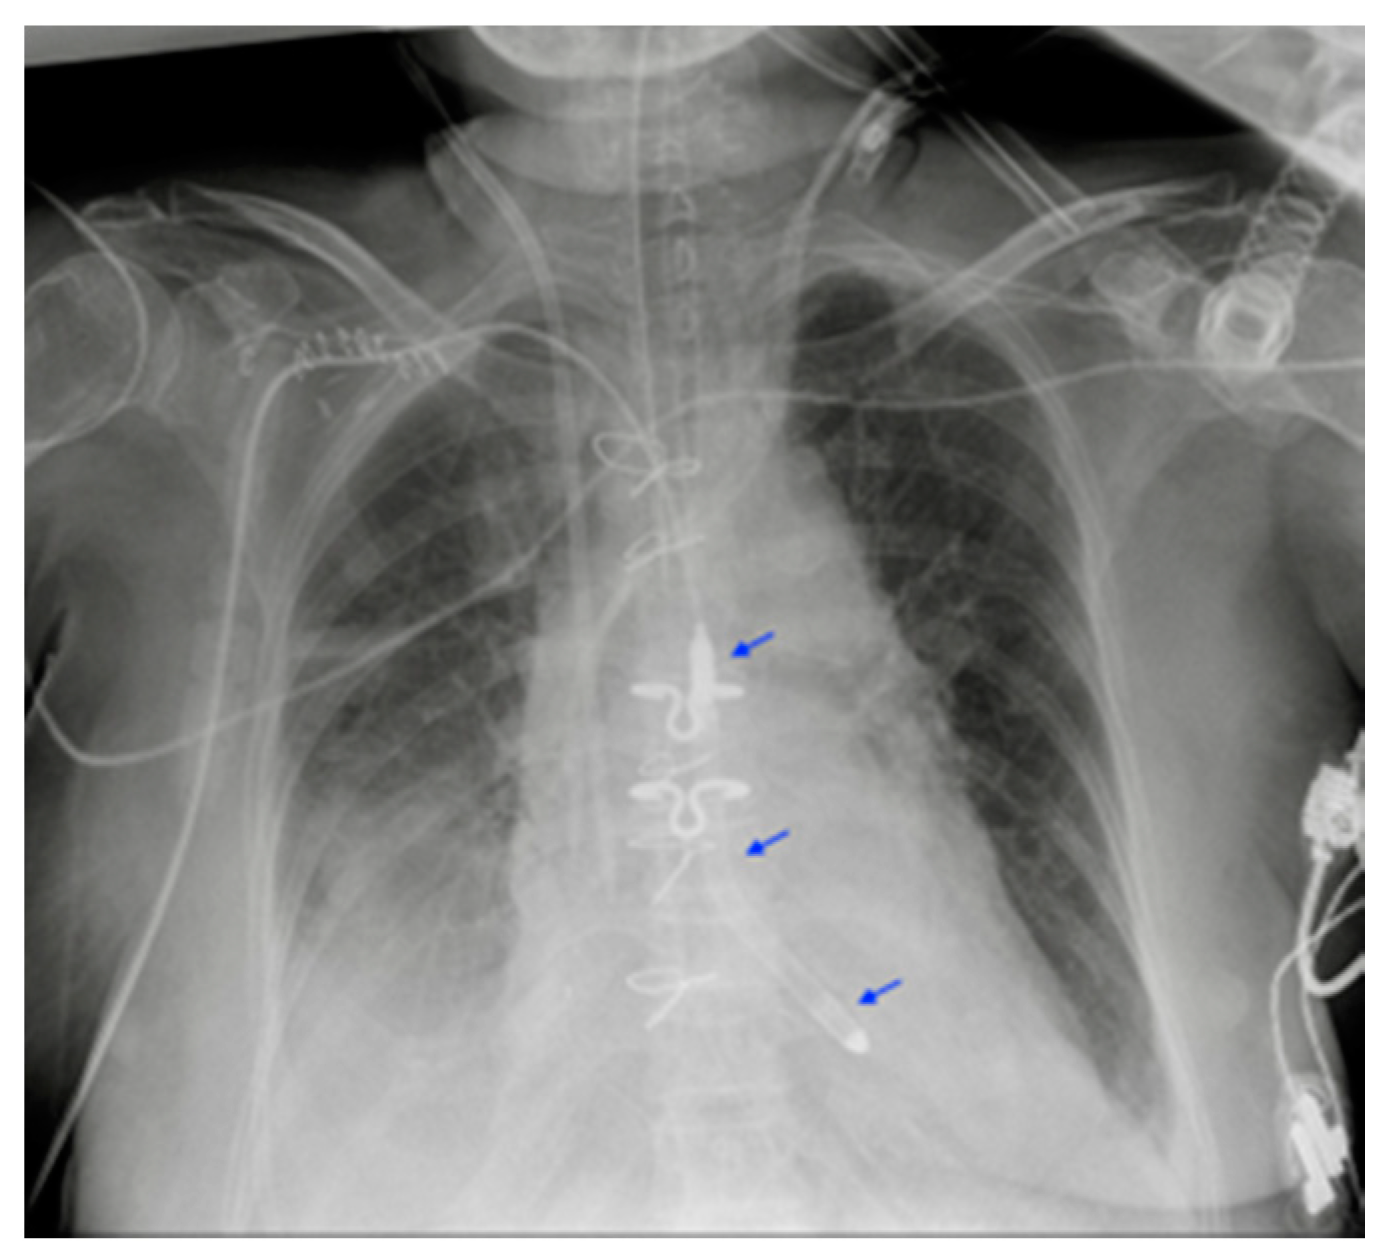

Figure 16.

Impella in the correct position. Device is placed into the left ventricle and in the ascending aorta through the aortic valve (blue arrows).